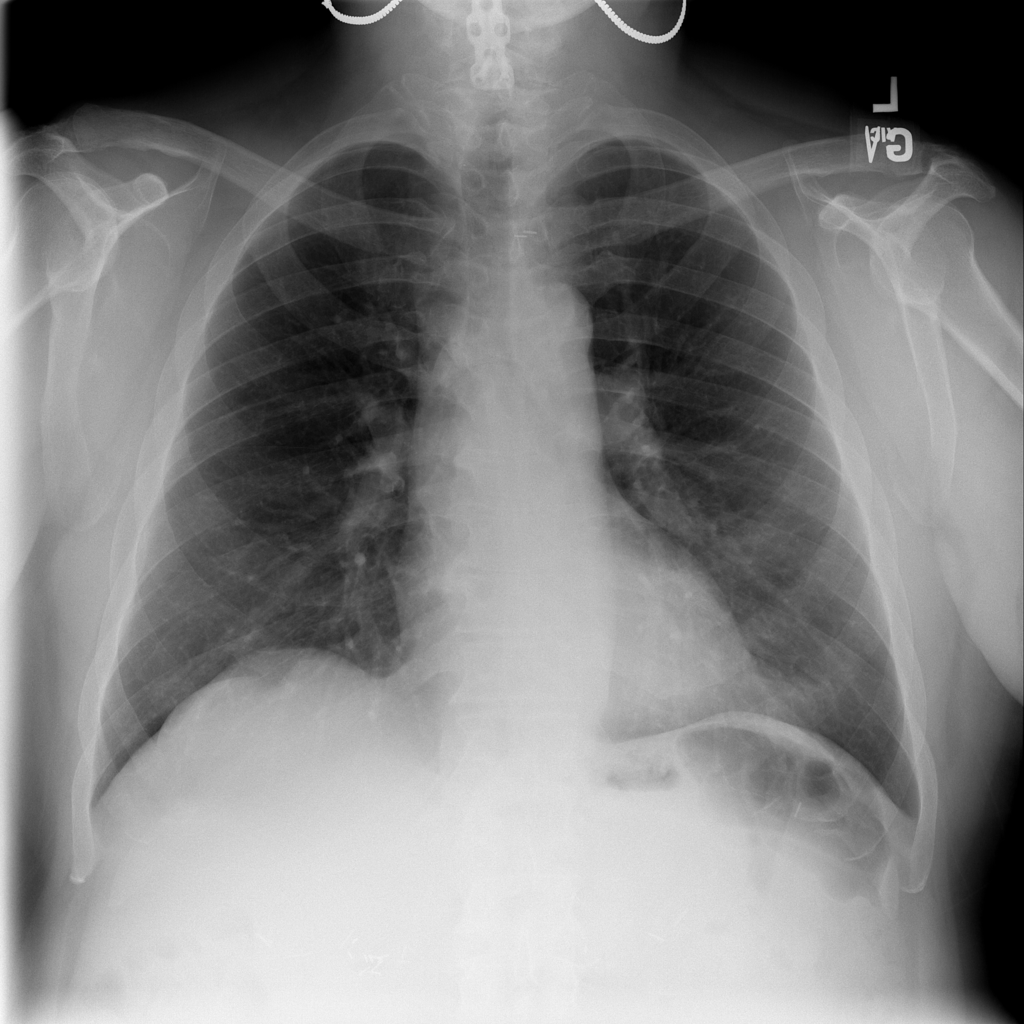

Nodule

A nodule is a small rounded opacity in the lung or chest field. It is a descriptive imaging finding that can be benign or more concerning depending on size, appearance, and context.

Showing up to 90 reference images for Nodule.

PAT-F3E7 · IMG-002Nodule

PAT-F3E7 · IMG-002

PA